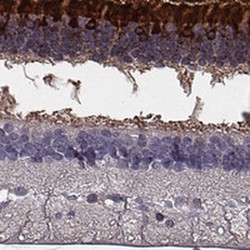

NBP2-58952 IHC

Immunohistochemistry